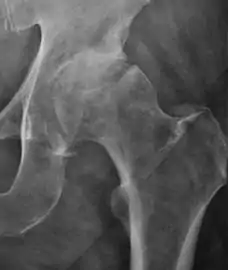

Plain radiography allows us to categorize the hip as normal or dysplastic or with impingement signs (pincer, cam, or a combination of both). Besides these, pathologic processes like osteoarthritis, inflammatory diseases, infection, or tumors can also be identified (Figure 1).[1]

Figure 1.

Radiography in normal hip

X-ray in pincer impingement type of hip dysplasia

X-ray of cam

Hip in osteoarthritis

Septic arthritis